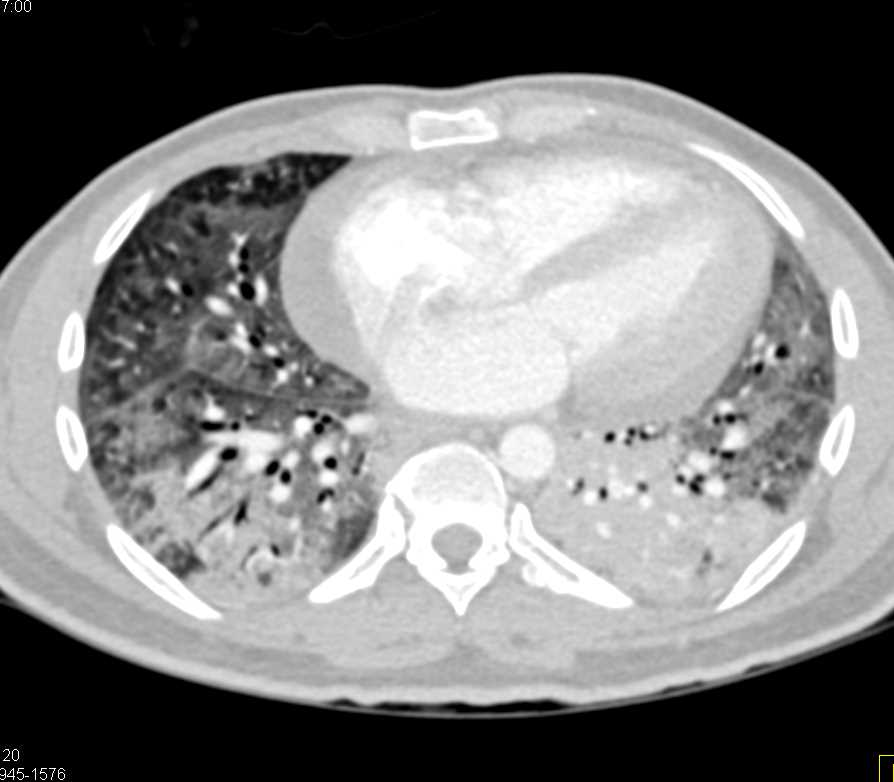

Metastatic Melanoma and Pulmonary Emboli (PEs)